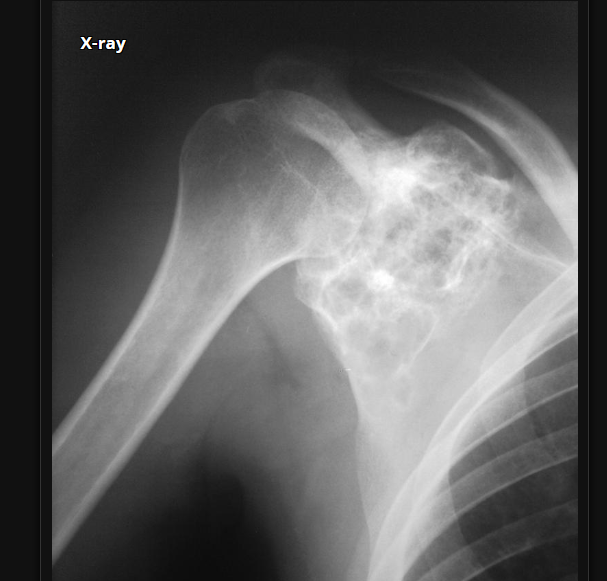

Cisto ósseo aneurismático

Acomete paciente jovem (fise aberta);

Localização excêntrica, aspecto em favo de mel no RX;

Pode ter reforço periosteal;

RM:lesão multicística; Septos + nível liquido-liquido (lesões dx diferencial: COS fraturado, COA, TCG ou osteossarcoma telangiectásico).

Primário ou Secundário à outros tumores: TCG, DF, Condroblastoma.